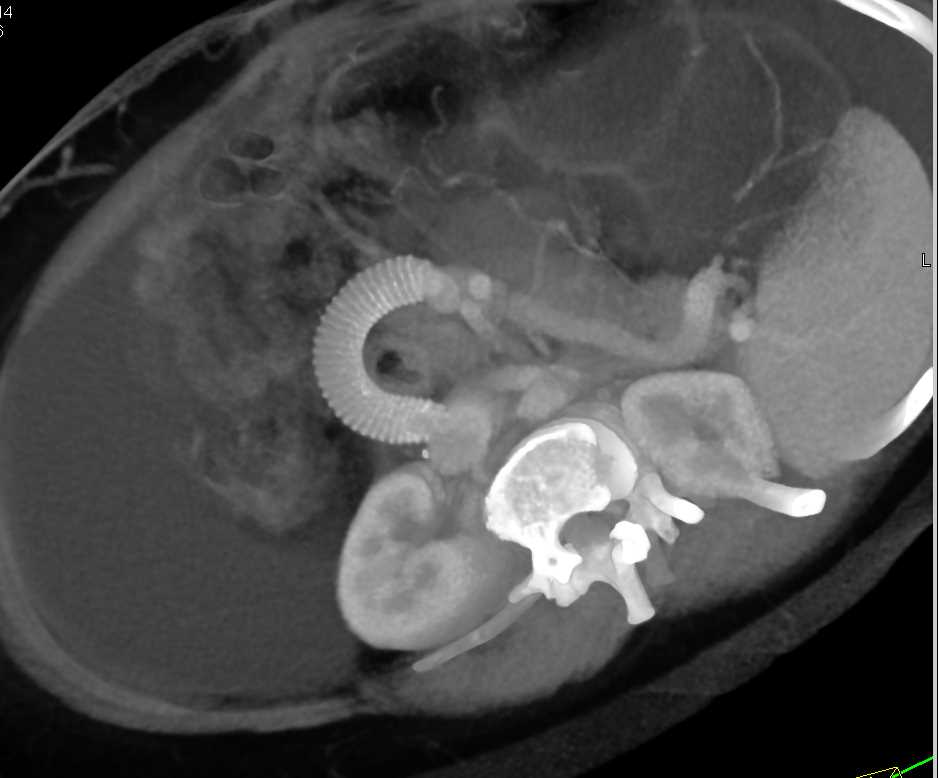

Portal Vein to Inferior Vena Cava (IVC) Stent in a Cirrhotic Patient